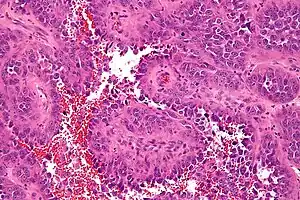

Uma vez que as células cancerígenas podem ser transportadas pelo sangue ou fluxo linfático, angiossarcomas podem mais facilmente metatizar para sítios distantes, particularmente o fígado e os pulmões.[3] A maioria dos tumores viscerais de parede de vasos sanguíneos e linfáticos são cancerosos (malignos). Hemangiossarcomas e linfangiossarcomas da pele não são comuns.[4] O sarcoma de Kaposi é um tipo de câncer que também é oriundo de células endoteliais.[5] Angiossarcomas mostram sinais de hemorragia e necrose. Patologicamente, células tumorais mostram maior relação núcleo-citoplasma, hipercromasia nuclear, pleomorfismo nuclear e alta atividade mitótica.[6]